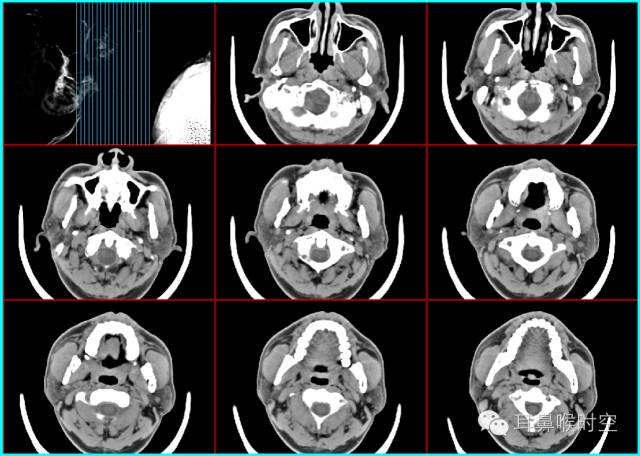

儿童腺样体肥大依据CT 表现分为3 型:

CT表现:

为鼻咽顶后壁增厚,形成肿块

前缘平直或略凹陷,堵塞后鼻孔

鼻咽腔变形、狭窄,上气道变窄。

临床表现:

为打鼾,张口呼吸,睡眠不安等。

CT 表现:

除Ⅰ型外

同时有上颌窦、筛窦黏膜增厚,窦腔变窄等慢性鼻窦炎表现及鼻甲肥大和/或鼻中隔偏曲

为鼻塞,流脓鼻涕及阻塞性睡眠呼吸暂停低通气综合征表现;

除Ⅰ型的CT表现外

还有咽鼓管咽口粘连狭窄及中耳乳突积液,即分泌性中耳炎表现。

文献报道,慢性鼻窦炎、腺样体肥大、咽鼓管非机械性阻塞等,都是小儿慢性分泌性中耳炎的常见病因。

为不同程度的听力下降甚至耳聋,耳聋为传导性耳聋。

标准CT 轴位像:

鼻咽气腔均不同程度变形变窄(图7,8) , 不规则形,横条形,完全闭塞。

增大的腺样体呈软组织密度,均匀一致,与头长肌相近,呈弥漫性肿块形(图9)、嵌入鼻后孔肿块形(图10)、单侧肿块形(图11)。

静脉增强扫描呈轻-中度强化。

鼻咽气腔形态

腺样体形态

弥漫性肿块形(图9) 嵌入鼻后孔肿块形(图10) 单侧肿块形(图11)